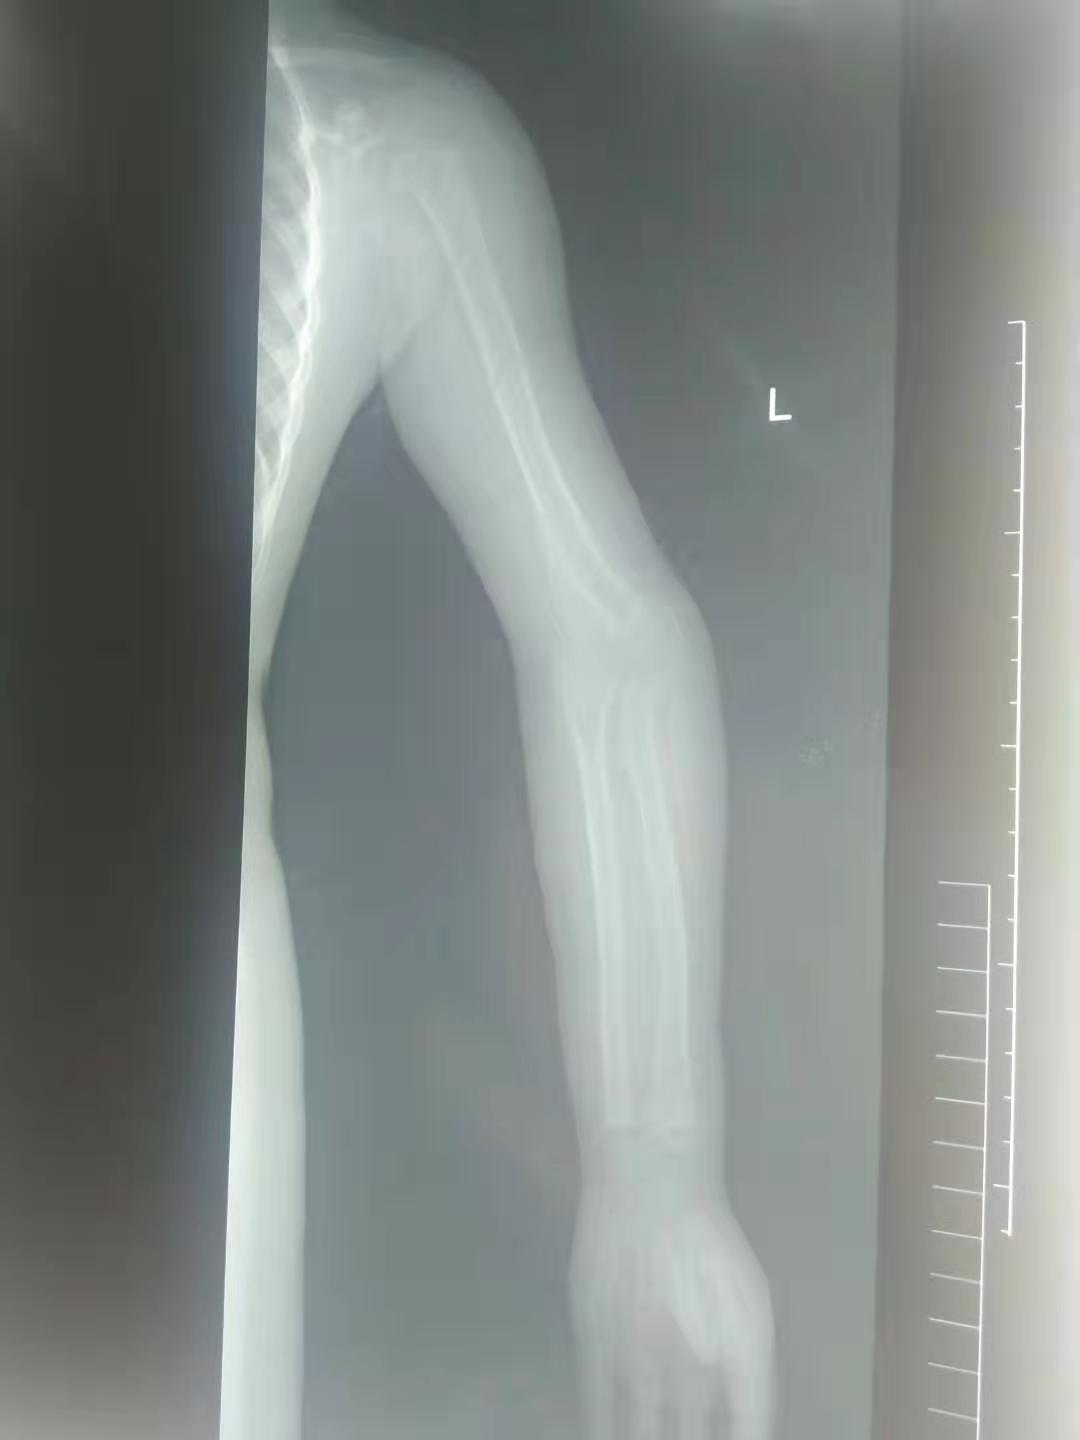

五岁的小女孩,因为小时候的意外导致了手肘骨折,当时不过一岁半的小女孩,没有及时告诉自己的妈妈,小女孩的妈妈发现了异常,小女孩手抬不起来,这可把这位妈妈给急坏了,立即带着孩子赶去了当地的医院,经过检查发现小女孩的手肘骨折错位,当时由于孩子太小,所以没有做手术,于是给予了手法复位,打了石膏,夹板;时隔两年,孩子的妈妈发现,孩子手肘与正常的手肘有些不一样,因为孩子太小,医生提议在孩子在大点的时候给予手术修型纠正。孩子的手有些畸形,没有出现什么功能障碍,只是对于一个孩子来说,影响外形。

骨折的手

对于儿童而言,骨折的愈合速度是成人的1/2,在幼儿期会更快,所以如果在骨折后没有很好的复位的话,对于年幼孩子来说,愈合后可能会导致肢体畸形或者功能障碍。有时候不同部位的骨折复位良好,也会出现因为本身愈合能力差的原因,导致不愈合性可能。

骨折不复位,容易破坏血液循环,形成骨不连,患者破坏小儿的骨骺,形成肢体生长畸形。